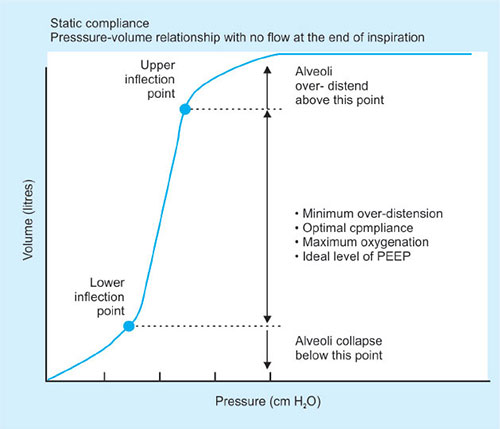

There are 2 types of compliance: static and dynamic

Static compliance is measured during plateau pressure.

Dynamic compliance varies and is calculated with measurement of tidal volume at a given intrathoracic pressure during which there is airflow through the lungs at any point during inspiration or expiration.

A variety of factors affect this like lung volume, pulmonary blood volume, extravascular lung water and pathological processes (inflammation, fibrosis)

Compliance can be measured by inserting an esophageal probe into a cooperative patient, the patient inhales and exhales to a set volume. At each volume the intrapleural pressure is estimated using the esophageal probe. A pressure volume curve can then be plotted. If during the measurement process no gas flow occurs at each set volume then this is static compliance. (Gas flow ceases and equilibration occurs.) If gas flow continues throughout measurement then this is dynamic compliance.